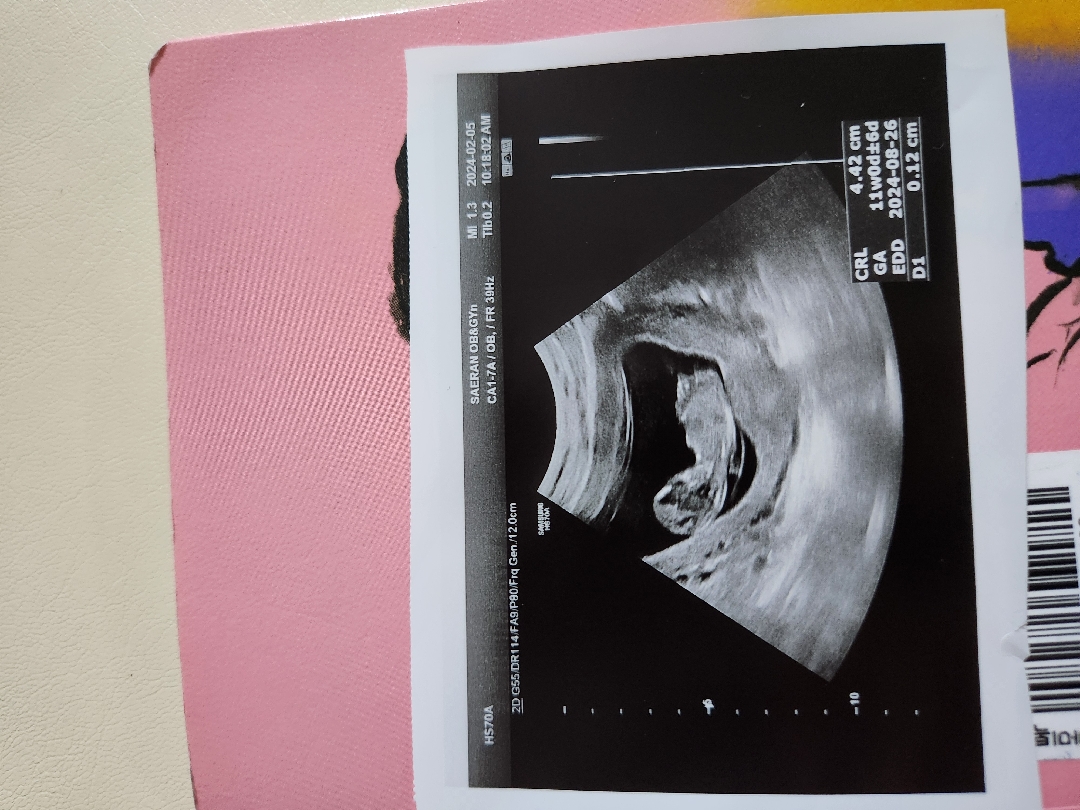

아기 뒷모습 같아요! 각도법은 옆모습으로 볼수 있어요!

각도법 봐주세욤~🙏

아~뒷모습 인것도 몰랐어요 알려주셔서 감사해용😍복 많이 많이 받으세용😍